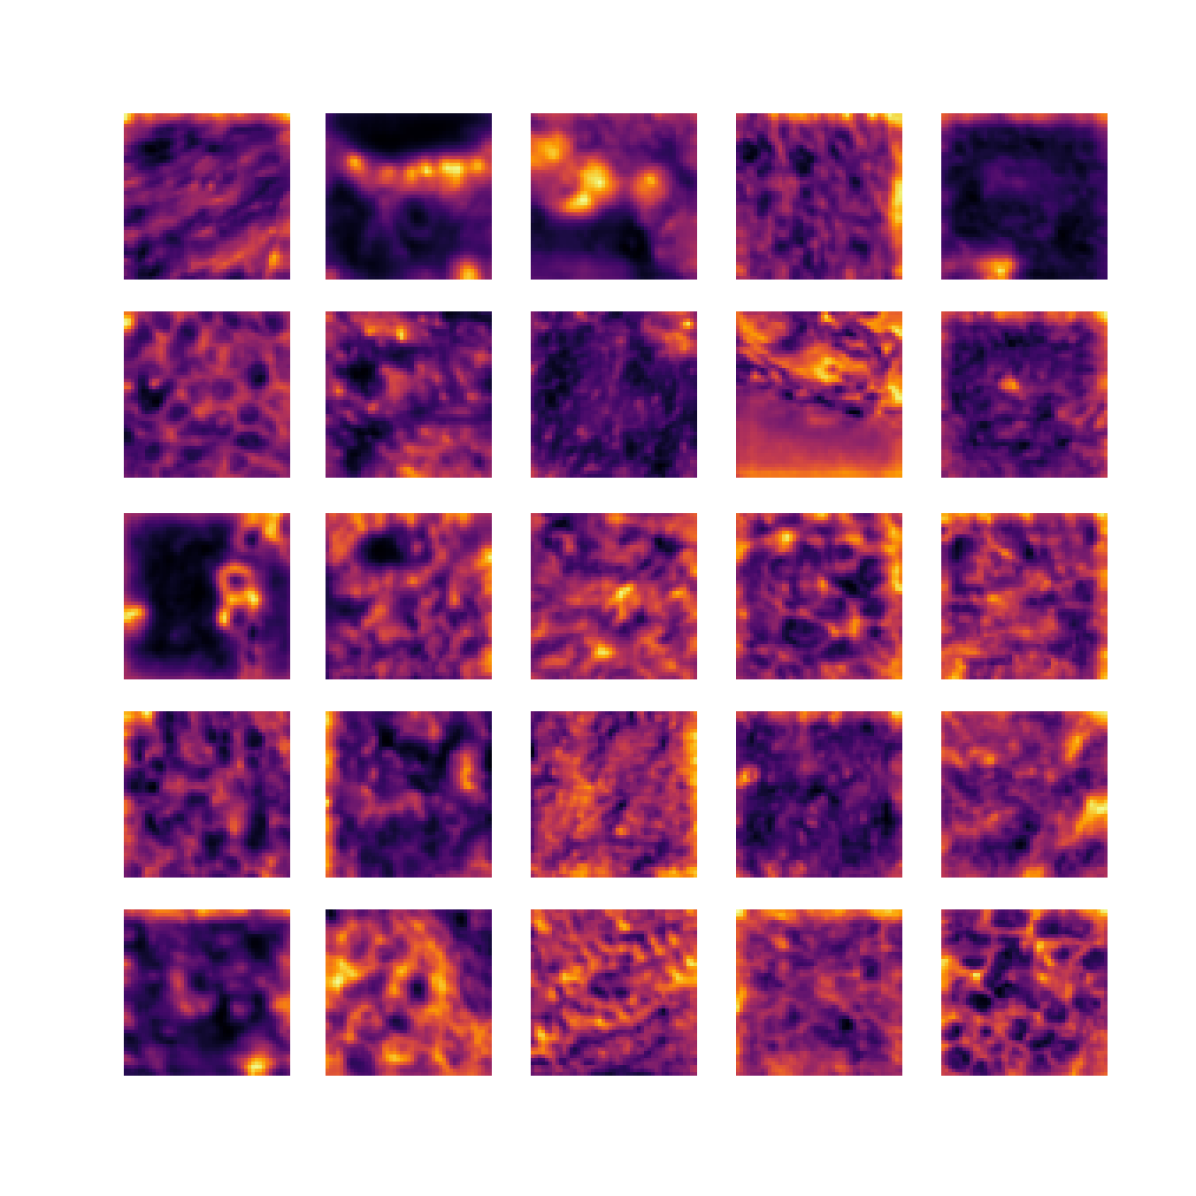

We also analyse the activation maps for each model using GradCAM as described in section S3. This offers more insight into the areas of the image which are contributing most heavily to the models’ representations. In Figure 4(b) we present some representative examples, however, a larger selection which was chosen at random is presented in Figures S10 to S25. The larger selection makes it easier to see the emergent patterns, including that privileged Siamese models tend to mainly identify features which are strongly present in both inputs, while unprivileged Siamese models tend to learn more diffuse features that are not specific to one cell phenotype or image region. TriDeNT ♆ incorporates both sets of features, learning both features specific to the privileged data and more the general features associated with unprivileged Siamese networks.

We can see in Figure 4(b) panel A that for ERG, the privileged Siamese model focuses almost exclusively on any nuclei which could be endothelial cells. As there are very few endothelial cells in the dataset, it could be an effective strategy to identify anything that could potentially be an endothelial cell to minimise the difference between the representations of the H&E model and the IF mask model. In the corresponding unprivileged Siamese image, we see that the model identifies some of these nuclei, albeit less strongly, but also focuses heavily on the other tissue and even the background, while strongly fixating on two spots of debris in the center of the image. This model has less ‘incentive’ to learn the weak features related to endothelial cells as these occur rarely and are not easy to detect, while more generic strong features such as the presence of connective tissue and the prevalence of background are more common and predictable from augmented images. We see that TriDeNT ♆ combines these two feature sets, strongly identifying nuclei while also identifying the connective tissue.

In panel C we see a similar pattern, with the privileged Siamese model fixating solely on the nuclei, while the TriDeNT ♆ model takes a more balanced approach. The unprivileged Siamese model appears to focus on a single cluster of nuclei while neglecting others, and similarly identifies an area of fibroblasts with its distinctive pattern but does not others.

In contrast to panels A and C which represent models with poor privileged Siamese results, panels B and D represent models whose privileged Siamese results were comparable to both TriDeNT ♆ and even the supervised baseline. It is therefore interesting to note that there are far more similarities between the privileged Siamese and TriDeNT ♆ models in both cases. Particularly in panel B, TriDeNT ♆ and the privileged Siamese model return virtually identical heatmaps, with both strongly identifying epithelial nuclei and neglecting the same areas of connective tissue. The unprivileged model in this case appears to focus solely on the centre of the image, giving a significantly different heatmap to the other panels.

Panel D again shows the previous pattern, with the privileged Siamese model identifying the features strongly present in the privileged data – fibroblasts – while neglecting the nuclei present. TriDeNT ♆ also strongly identifies the connective tissue, but, unlike the privileged Siamese model, does not completely neglect the nuclei. The unprivileged Siamese model primarily identifies background, and does not appear to identify the nuclei in this example.